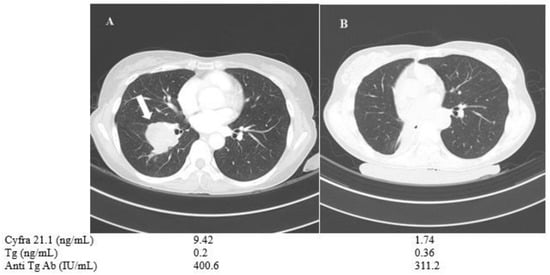

A 57-year-old female (patient No. 1) who had PDTC with negative BRAF mutation showed no detectable Tg or anti-Tg antibody levels, despite multiple lung metastases. Tg or anti-TgAb measurement is useless in verifying the disease progression in these cases of Tg non-secretary PDTC. Therefore, serum Cyfra 21.1 was used as an alternative tumor marker. It was monitored during disease progression under lenvatinib therapy. Serum Cyfra 21.1 was increased from 1.87 to 5.24 ng/mL when the total tumor size of three metastatic lung nodules showed a 33% increase based on RECIST criteria, while the serum Tg and anti-TgAb levels showed minimal change (Figure 4).

Figure 4.

Changes in chest CT images and serum biomarkers of a 57-year-old female with poorly differentiated thyroid cancer (patient No. 1) before (A) and after one year of TKI treatment (B).